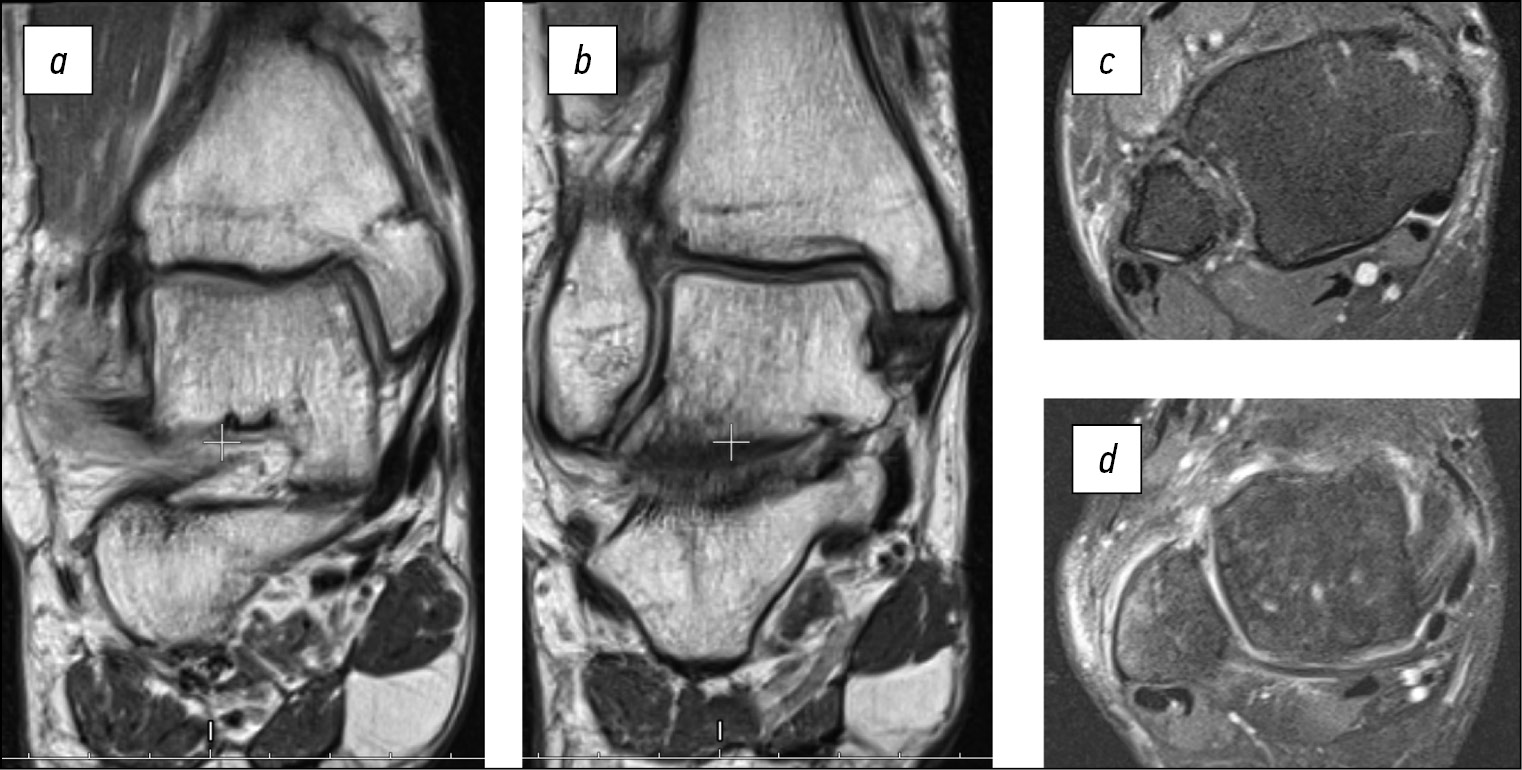

На магнитно-резонансных томограммах (МРТ) правого голеностопного сустава во фронтальной плоскости в режиме Т1 наблюдаются несросшийся перелом внутренней лодыжки, разрыв поверхностной (рис. 1a) и глубокой (рис. 1b) порций внутренней коллатеральной связки. На компьютерной томограмме (КТ) правого голеностопного сустава в кософронтальной плоскости (рис. 1c) наблюдаются консолидированный со смещением отломков по ширине перелом дистальной трети диафиза малоберцовой кости, несросшийся перелом внутренней лодыжки, подвывих стопы кнаружи. На МРТ правого голеностопного сустава в аксиальной плоскости в режиме Т2 наблюдаются разрыв передней и задней межберцовых, межкостной связок с признаками рубцевания, латеропозиция наружной лодыжки относительно малоберцовой вырезки большеберцовой кости (рис. 1d), разрыв глубокой порции дельтовидной связки с признаками рубцевания (рис. 1e).

Рис. 1. a, b — магнитно-резонансные томограммы пациентки В. на момент поступления во фронтальной плоскости в режиме Т1, c — компьютерная томограмма в кософронтальной плоскости, d, e — магнитно-резонансные томограммы в аксиальной плоскости в режиме Т2

Fig. 1. a, b — preoperative coronal T1 magnetic resonance imaging of patient B., c — oblique-frontal plane computed tomography scan, d, e — axial T2 magnetic resonance imaging

На МРТ правого голеностопного сустава во фронтальной плоскости в режиме Т1 через 6 месяцев после оперативного вмешательства наблюдаются зрелые рубцы, соответствующие по длине и позиции поверхностной (рис. 3a) и глубокой (рис. 3b) порциям внутренней коллатеральной связки. На МРТ в аксиальной плоскости в режиме Т2 наблюдаются зрелые рубцы, соответствующие по длине и позиции межберцовым связкам (рис. 3c) и глубокой порции внутренней коллатеральной связки (рис. 3d).

Рис. 3. Магнитно-резонансные томограммы пациентки В. через 6 месяцев после оперативного вмешательства: a, b — во фронтальной плоскости в режиме Т1, c, d — в аксиальной плоскости в режиме Т2

Fig. 3. 6 months postoperative magnetic resonance imaging of patient B.: a, b — T1 in coronal plane, c, d — T2 in axial plane

Клинический случай демонстрирует эффективность применения аппарата Илизарова как самостоятельного метода лечения застарелого подвывиха стопы.